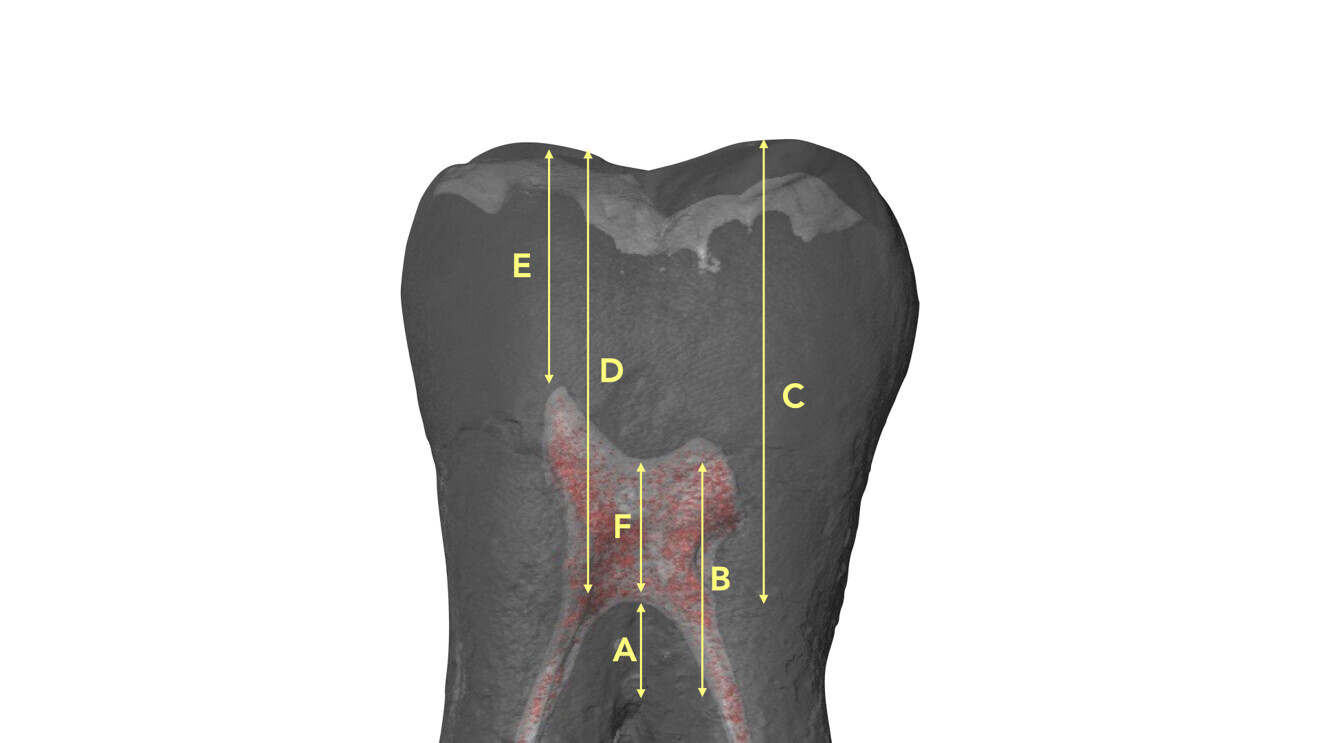

This refers to the use of a specific type of diamond bur for the penetration step, in particular for maxillary and mandibular molars and maxillary furcated premolars. Deutsch et al. determined morphological measurements concerning the relationship between the occlusal surface and the height and position of the roof and the floor of the pulp chamber in multi-rooted teeth.8, 9 In these teeth, the roof of the pulp chamber is located at the CEJ. In molars, the distance between the top of any cusp and the roof of the pulp chamber is approximately 6.30 mm, and in maxillary furcated premolars, it is 6.94 mm. The pulp chamber of maxillary and mandibular molars has a height of approximately 1.5–2.0 mm, and the average distance from the floor of the chamber to the furcation is approximately 3.0 mm (Table 1; Fig. 13). A more recent publication confirmed these measures employing a micro-CT analysis.10 This means that dentists can rely on plenty of data to approach each root canal therapy in a rational and predictable way.

Fig. 13: Locations of the measurements performed by Deutsch et al. on a micro-CT scan of a mandibular molar.8, 9 A = pulp chamber floor to furcation; B = pulp chamber roof to furcation; C = buccal cusp to furcation; D = buccal cusp to pulp chamber floor; E = buccal cusp to pulp chamber roof; F = pulp chamber height.8, 9 (Image: Elio Berutti)